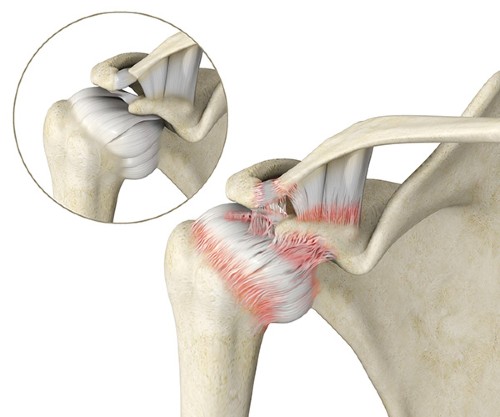

A articulação do ombro é composta por uma estrutura chamada de cápsula articular, que é elástica e flexível, por apresentar colágeno em sua composição.

A capsulite adesiva é um processo inflamatório que afeta a cápsula articular do ombro, causando dor, contratura muscular e rigidez articular, dificultando a execução de movimentos que dependem do ombro.

Dentre essas estruturas, está a cápsula articular que, como o nome sugere, envolve toda a articulação, conferindo proteção e estabilidade. Como esta estrutura é flexível, ela permite a movimentação da articulação em grande amplitude e em várias direções.

A cápsula articular pode sofrer um processo inflamatório decorrente de problemas que podem afetar os membros superiores ou o próprio ombro, como uma infecção ou uma luxação.

Assim, a capsulite adesiva é a inflamação da cápsula articular, que resulta em seu inchaço, vermelhidão, espessamento e perda da elasticidade.

A capsulite adesiva pode ser causada por inflamações que afetam os tendões ao redor dos ombros (tendinite) ou por rupturas parciais ou totais dos mesmos.